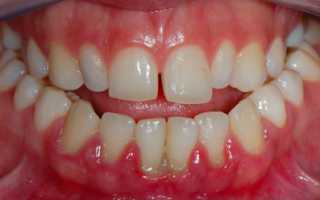

Ювенильный или юношеский

Встречается в основном у подростков в локализированной форме. Согласно статистике, чаще всего подвержены заболеванию именно девушки. Протекает пародонтит этого типа практически бессимптомно.

Возникает даже из-за небольшого количества налета. Причины появления пародонтита такой формы — грамотрицательные анаэробные бактерии. Заболевание приводит к вертикальной потере кости у первых моляров.

Нередко воспаление захватывает резцы. Дёсны при начале болезни краснеют, появляется несильный зуд.